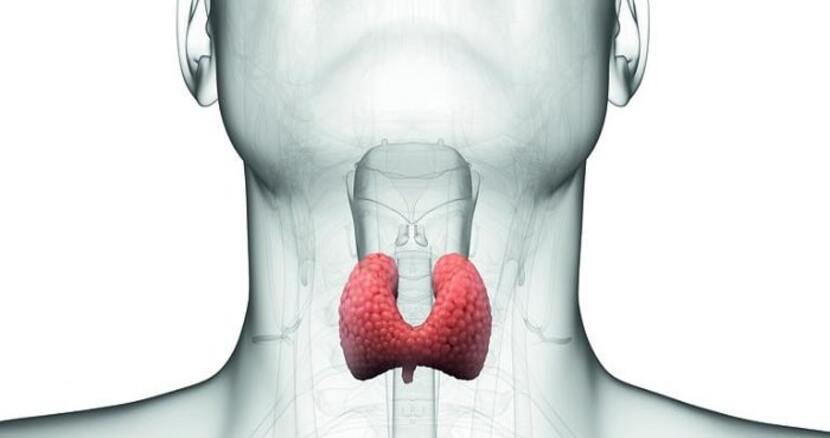

تیروئید یک غده پروانهایشکل در جلوی گردن است که تولید هورمون، کنترل متابولیسم و عملکرد ماهیچهها و گوارش را بر عهده دارد.